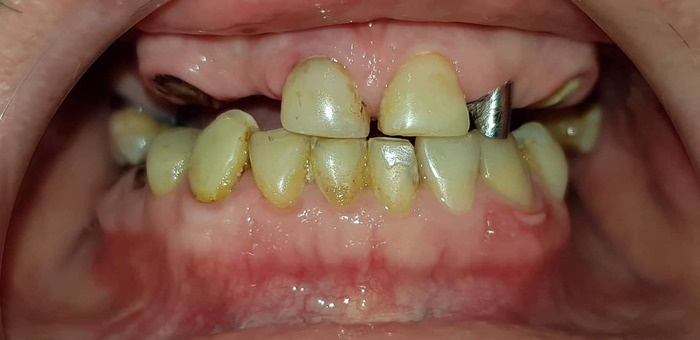

Теперь - как это все дело выглядело в реале:

Вот честно, пока я не увидел именно эти две фотки - я слабо осознавал, какой именно у меня пипец во рту. Каждое утро в зеркале это воспринималось немного не так. Передергивало, конечно, но было привычно. Кстати, все эти фото я увидел уже сильно после лечения и никакого влияния на мое решение лечиться у Георгия они не оказали - не успели )))

Это я. До начала лечения вообще.